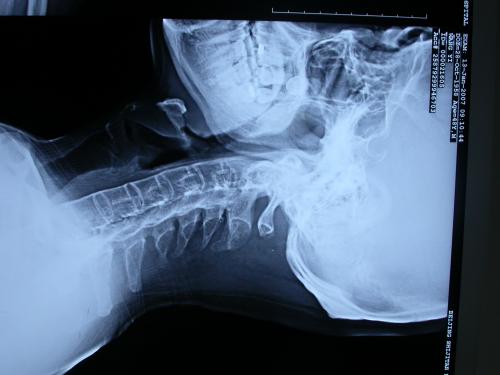

骶髂关节(即为腰臀部的大关节)为本病最早发病的部位,所以对怀疑有强直性脊柱炎者,医生会拍骨盆正位片、腰椎的正、侧位片,必要时会做CT、放射性核扫描、磁共振等影像学检查。